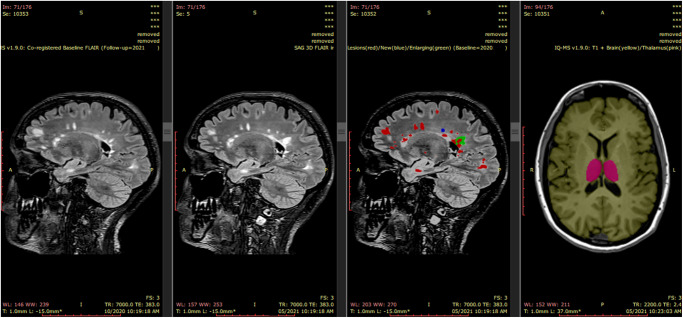

iQ-Solutions™ analyses brain MRI scans in Digital Imaging and Communications in Medicine (DICOM) format using a collection of AI algorithms based on deep neural network technology, and was developed using more than 8500 brain scans that had been expertly annotated by trained neuroimaging analysts. iQ-SolutionsTM produces an MS-specific report that includes cross-sectional and longitudinal whole brain, brain substructure and lesion metrics relevant to the condition (Table 1). The AI tool returns visualizations of relevant segmentations to the PACS for radiologist review (Fig. 1).

Fig. 1. iQ-SolutionsTM PACS integration.

iQ-MS automatically returns a co-registered baseline (prior study) 3D FLAIR series together with a lesion-annotated 3D FLAIR, here showing a case with both new (blue) and enlarging (green) lesions. A 3D-T1 series is also returned with both whole brain (yellow) and thalamus (pink) annotations. From left to right images : Co-registered FLAIR from patient’s last scan; FLAIR image of the current MRI exam; Lesion masks overlaid on current FLAIR image; Brain and Thalamus masks overlaid on current 3DT1 image.